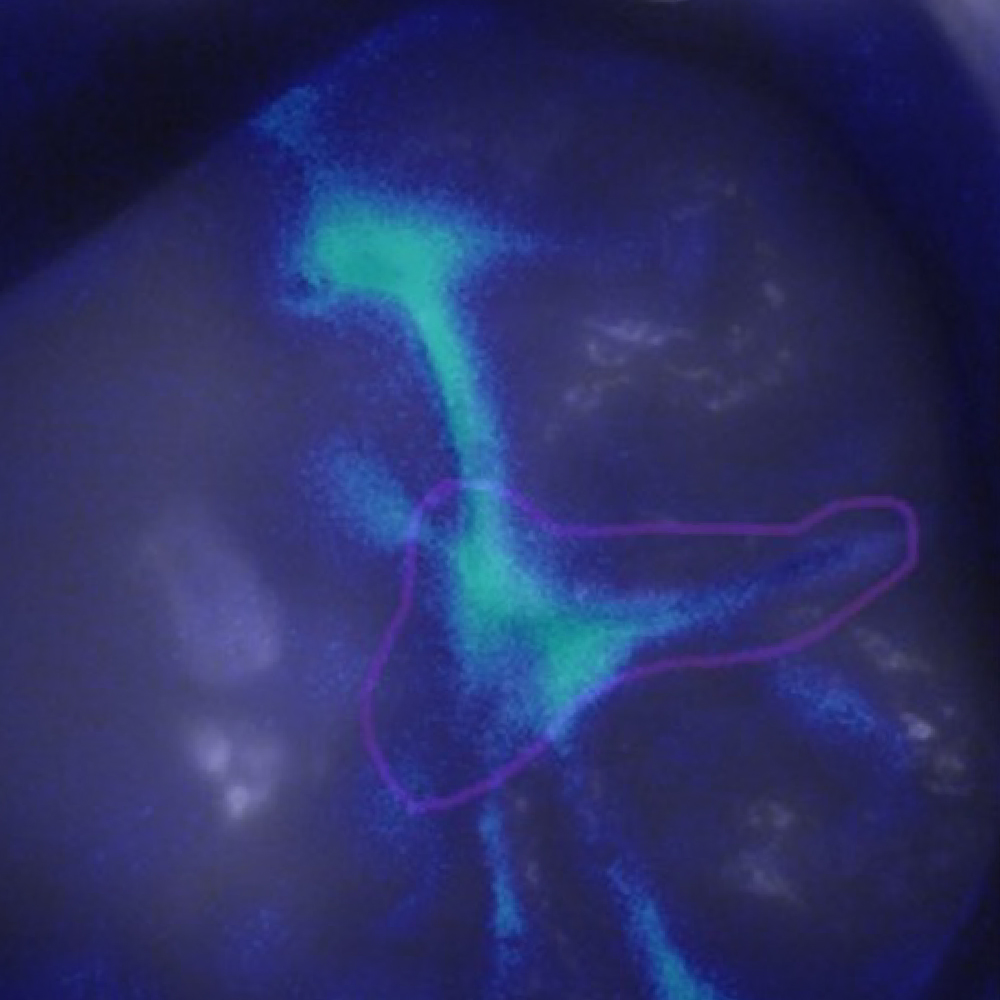

IMAGE 1

Can you differentiate?

3

MODERATE

Quiz Image Overlay Overlay

Prevention/Treatment Pathway Options

If no or minimal signs of dentinal caries involvement on radiography or transillumination – Fissure Sealant;

if signs of moderate dentinal caries, fissurotomy exploration and Sealant or Sealant-restoration;

Assess all other molars with Calcivis Imaging.

Supported by:

• Fluoride for prevention (all teeth)

• OHI/Education

• Regular screening with Calcivis Imaging

Please observe that the mesial of this tooth has a bioluminescence signal but no obvious demineralization on the tooth surface.